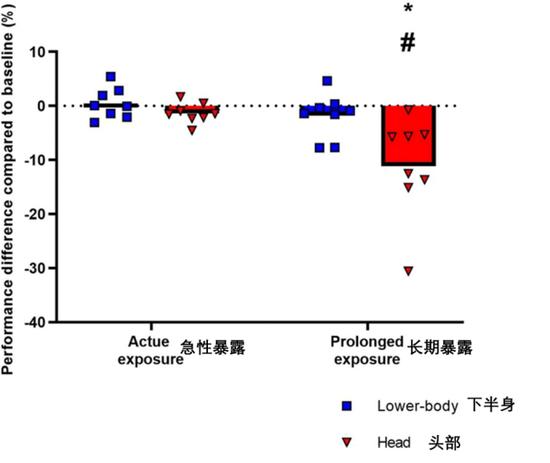

如下图显示,头部长时间(2小时)暴露于模拟阳光下的受试者进行复杂运动和综合运动认知任务的分数明显降低。相反,急性暴露(15分钟)或者持续的下半身加热都没有导致运动认知能力的下降。

总的来说,本次研究发现长时间施加于头部的辐射热会一定程度上影响大脑的机能,特别是在复杂运动和组合运动认知测试中,受试者的能力都表现出相当明显的衰减。头和颈部直接暴露于辐射热主要影响大脑的浅表部分。但即便仅仅是大脑浅表处的温度升高,都会对人脑的短期能力产生损害。作为对比,当下半身的辐射暴露引起身体深部核心温度相似的升高时,则不会引起明显损伤。另外,头和颈部的短期急性暴露会立即使颅外(皮肤)温度升高,但并未对大脑的机能产生明显的影响。